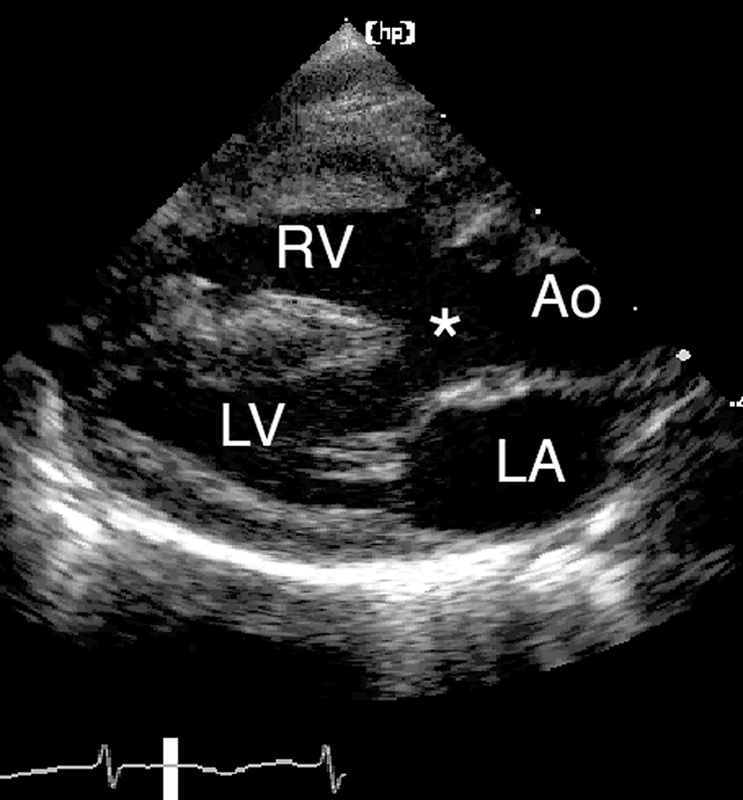

فحوصات تشخيصية لبعض امراض القلب والشرايين التاجية